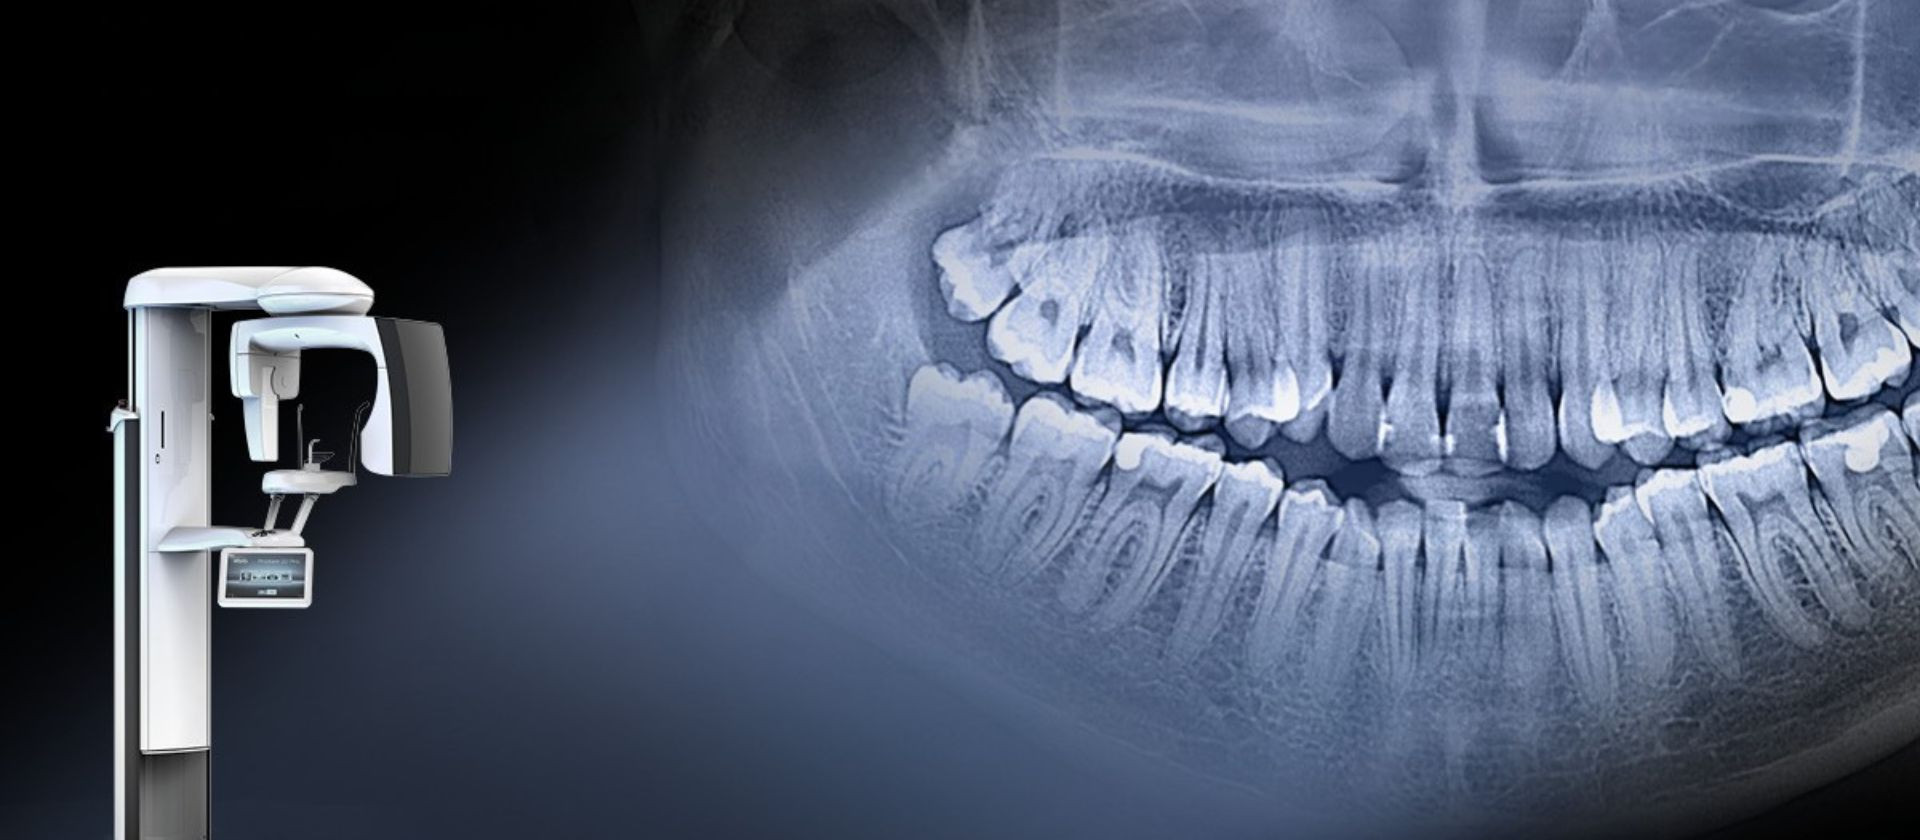

Captures every detail.

Disfrute de la combinación perfecta entre la tecnología de rayos X moderna y el soporte de software inteligente: la tecnología de imagen KaVo ProXam y las herramientas basadas en IA de Romexis permiten obtener imágenes que muestran más allá de lo obvio.